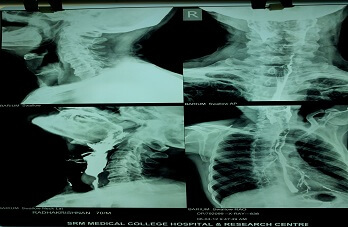

He completed his Diplomate National Board form National Board of examinations. With love for teaching young medical students, he worked as Associate Professor, Department of ENT, SRM Medical college, Kattangulathur. He has since started practicing on his own to provide optimum care with respect to ENT ailments.